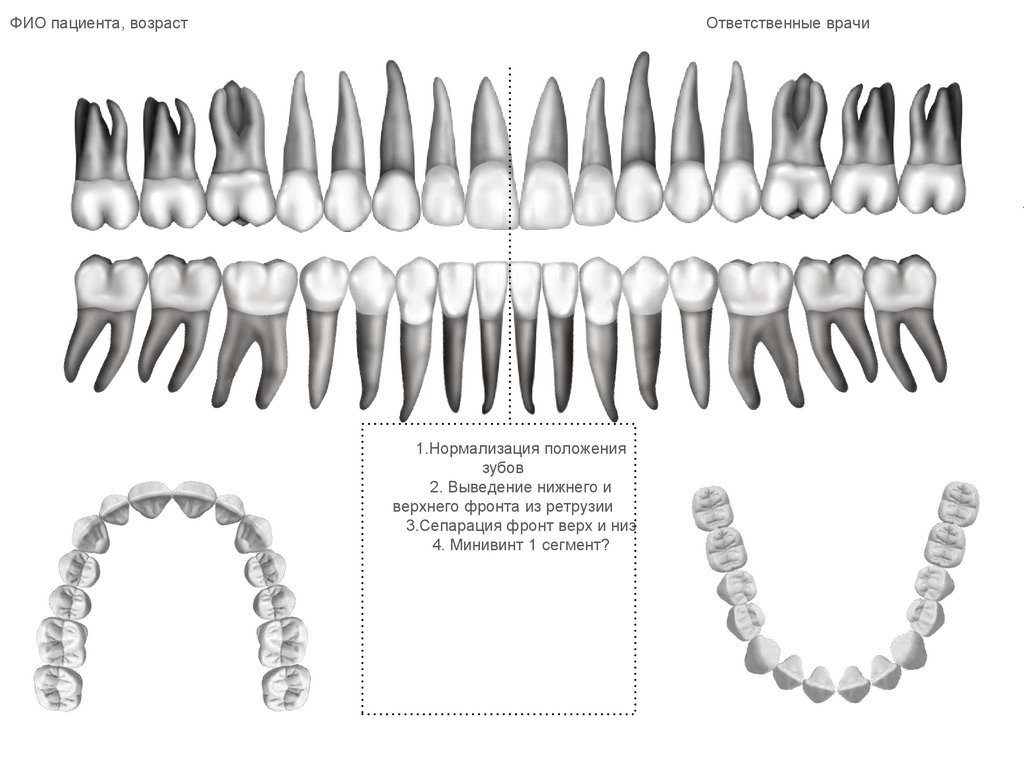

ФИО пациента, возраст

Ответственные врачи

1.Нормализация положения

зубов

2. Выведение нижнего и

верхнего фронта из ретрузии

3.Сепарация фронт верх и низ

4. Минивинт 1 сегмент?